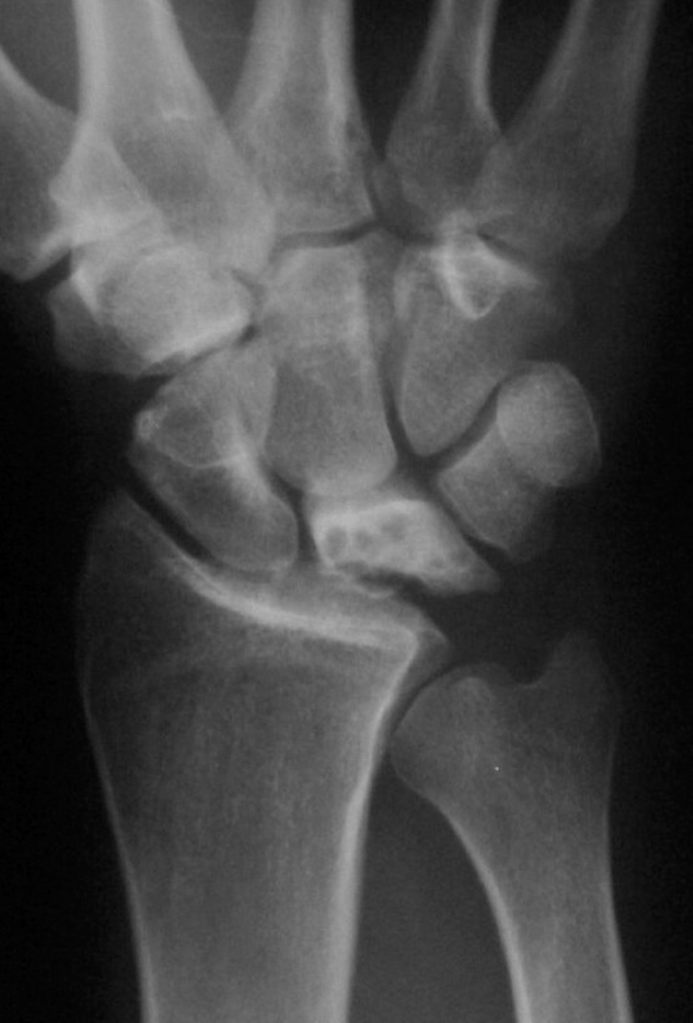

It is actually difficult to determine what will be the natural history of Kienbock’s disease in patients who first present. The condition is sometimes diagnosed very early on, before any xray changes are seen. In other patients the condition presents when the lunate bone fractures or breaks because of bone death.

Kienbock’s disease can be classified according to the changes seen on xrays and scans, and we try to classify the condition in all patients, so that we can give an idea of what is likely to happen. If, for example, a patient presents with stage 2 Kienbock’s, but 6 months later has progressed to stage 3, then we assume that the disease process is active. If no progression of the condition is seen on serial xrays, then we can say that the disease process is static.